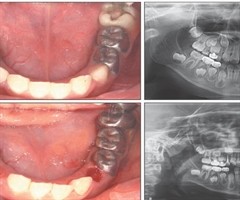

乳磨牙萌出障碍的临床表现分析

中图分类号] R788 [文献标志码] A [doi] 10.7518/hxkq.2025.2025108 [摘要]目的基于口腔曲面体层片,分析乳磨牙萌出障碍的发生率、影像学特点及临床伴随症状,为乳磨牙萌出障碍的诊疗提供依据。方法回顾202...